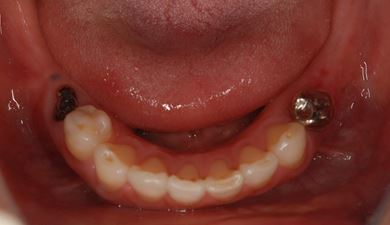

インプラントの症例写真 IMPLANT

インプラント治療+セラミック治療

| 治療内容 | インプラント2本、メタルボンドセラミッククラウン4本、ジルコニアフレームオールセラミッククラウン1本(オールセラミック用土台1本) | ||||||||||||||||||||||||||||||||